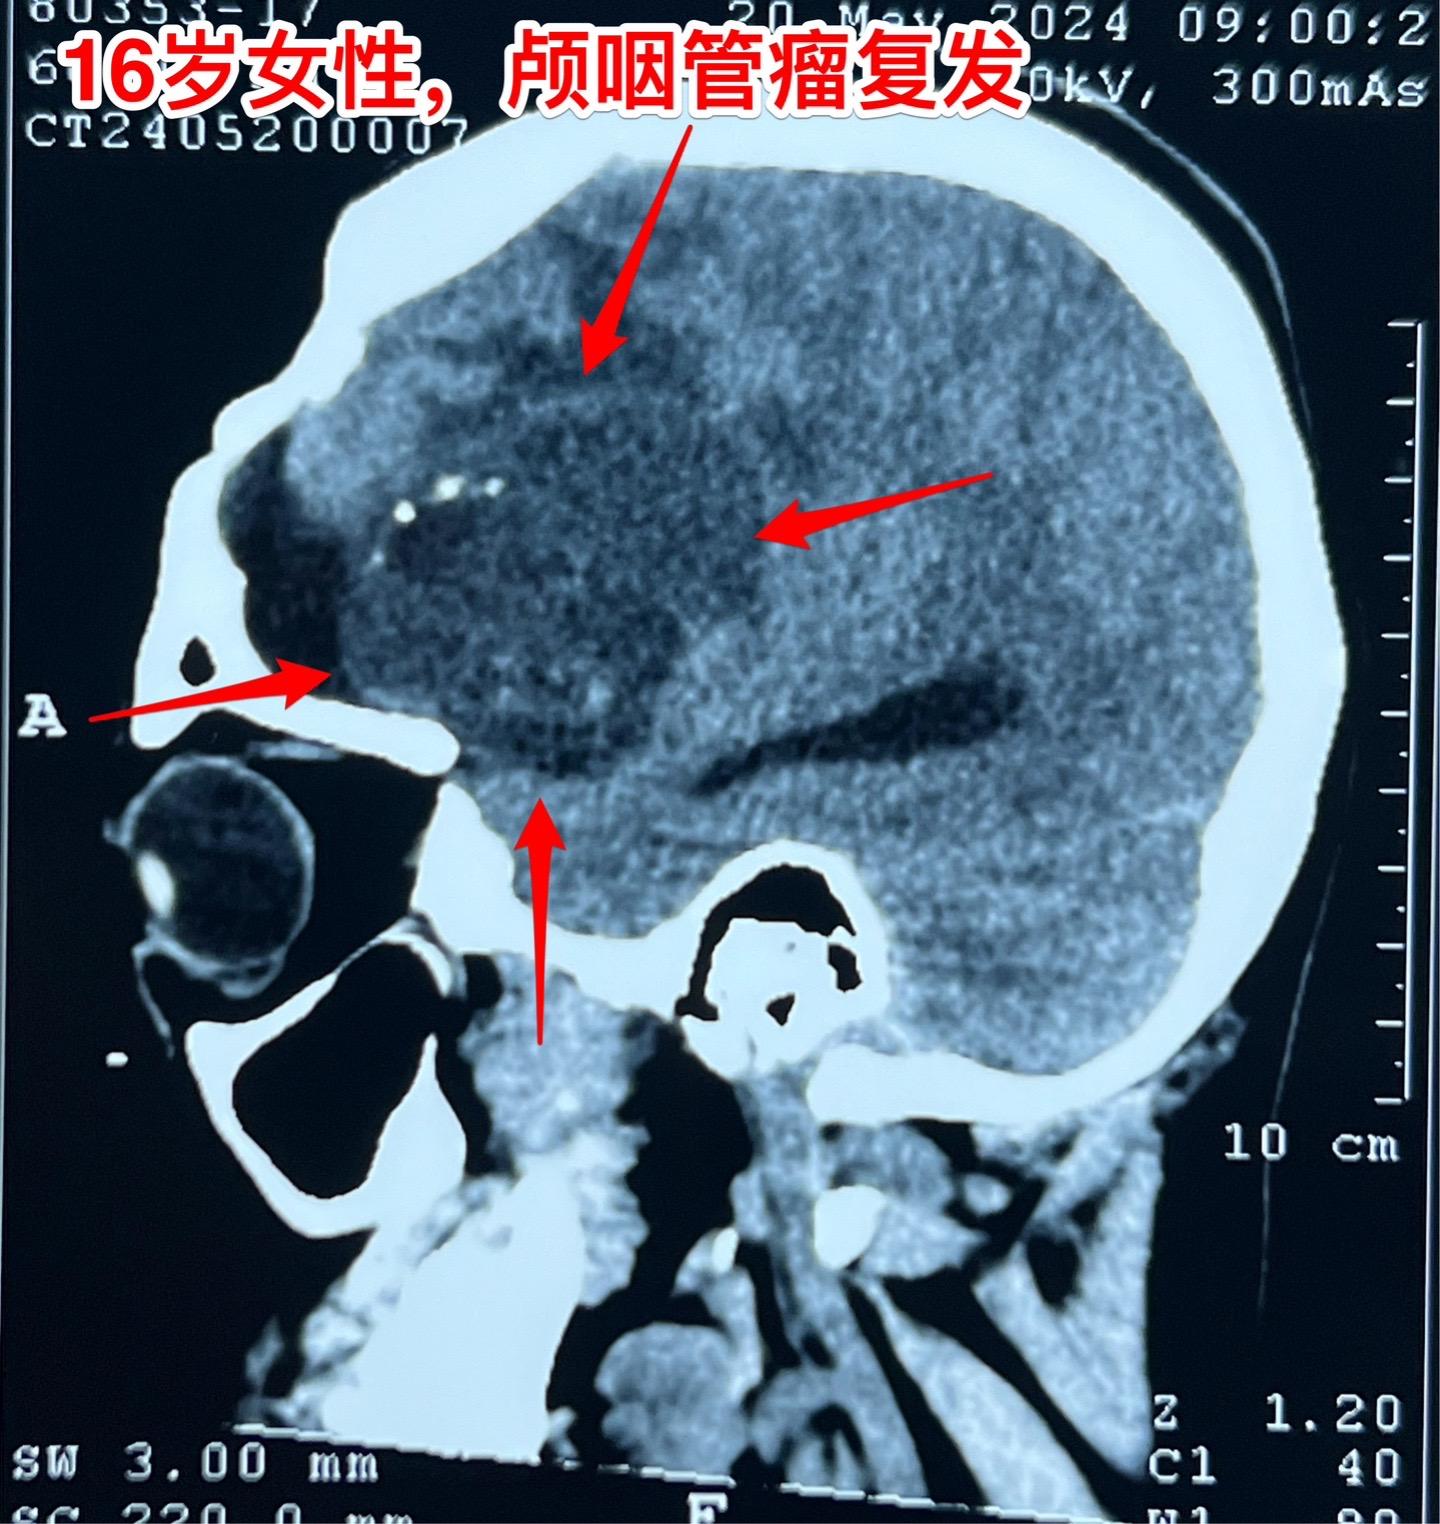

16岁女生颅咽管瘤第三次手术。第二次手术是在2013年1月。那次手术后还因脑积水作了脑室腹腔分流术。出院后能上学读书,而且内分泌方面还不错。有点遗憾的是额部手术疤痕及颅骨变形影响了病人的容貌。 这次的手术原计划在5月28日进行,因为她的生理周期突然提前了(自然的周期)故而将手术推迟到6月4日进行。肿瘤得到完全切除。 这次的肿瘤体积很大,但是还没有影响到垂体-下丘脑,可以预见,她的内分泌功能不会受到破坏。只希望她的肿瘤不再复发。内分泌

16岁女生颅咽管瘤第三次手术。第二次手术是在2013年1月。那次手术后还因脑积水作了脑室腹腔分流术。出院后能上学读书,而且内分泌方面还不错。有点遗憾的是额部手术疤痕及颅骨变形影响了病人的容貌。 这次的手术原计划在5月28日进行,因为她的生理周期突然提前了(自然的周期)故而将手术推迟到6月4日进行。肿瘤得到完全切除。 这次的肿瘤体积很大,但是还没有影响到垂体-下丘脑,可以预见,她的内分泌功能不会受到破坏。只希望她的肿瘤不再复发。颅咽管瘤内分泌